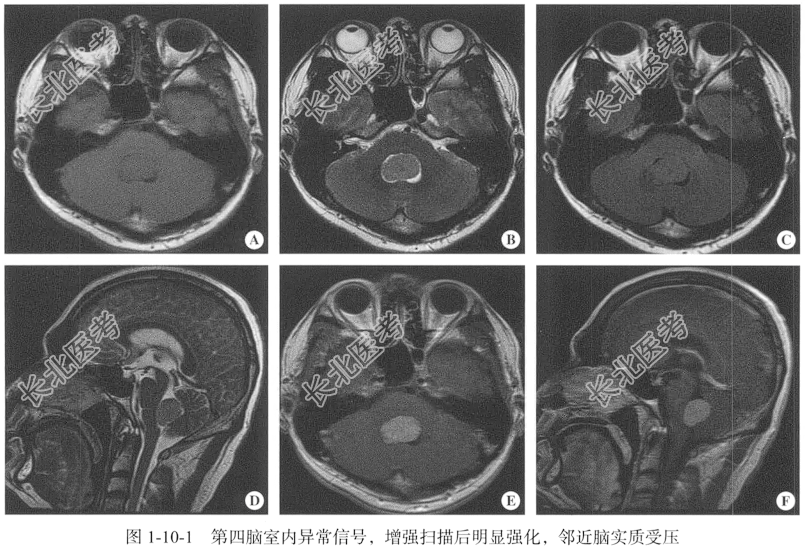

- [材料题] 【临床病史】男性,38岁。头晕半年,加重伴视物重影20余天。

【专科查体】患者神志清,精神可,定位定向准确,查体合作,双侧病理反射阴性,脑膜刺激征阴性。

【头颅MRI检查】仰卧位,横断位扫描,包括T₁WI、T₂WI及T₂FLAIR序列,扫描范围自颅顶至小脑下缘以下,扫描层厚为5.00mm,层间隔0.50mm,矩阵512×512;辅以矢状位T₂WI序列,平扫后行横断位、冠状位及矢状位的增强扫描。

【影像图片】见图1-10-1。

【手术所见】第四脑室肿瘤与脑干组织界线不清,颜色呈灰白、灰红,质软,基底位于脑干,大小约3.00cm×2.00cm。

【病理所见】第四脑室不整组织一堆,大小约为3.00cm×2.50cm×1.00cm,呈灰白、灰红色,质软。镜下示大量真性乳头结构被纤维结缔组织分割,乳头的纤维血管轴心被立方细胞围绕,细胞核呈圆形或卵圆形,位于上皮细胞基底部,核分裂象罕见(图1-10-2)。免疫组化结果:AE1/AE3(-),S-100(+),CK19(-),TTF-1(-),Napsin A(-),Ki-67(2%+),GFAP(+),CK7(灶+),EMA(-)。

【病理诊断】结合形态学及免疫组化结果,诊断为脉络丛乳头状瘤。